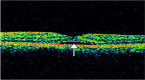

The authors report a case of a 46-year-old Hispanic male with central serous chorioretinopathy (CSC) following blunt trauma to the left eye. The patient presented with a complaint of throbbing headache and blurry vision in left eye. The patient was diagnosed with diabetes mellitus 1 year previous to the event. On examination, uncorrected visual acuity was 20/20 OD, 20/200 OS. No anisocoria or afferent pupillary defect was present. Intraocular pressure was normal. Subconjunctival haemorrhage and lid ecchymosis were present in OS and fundus examination showed serous macular detachment and central retinal pigment epithelium detachment, and no evidence of diabetic retinopathy. Optical coherence tomography OS showed subretinal fluid and fluorescein angiography demonstrated the typical 'smokestack' pattern of leakage into the subretinal space. The patient received observational therapy for 4 months and the CSC spontaneously resolved with visual acuity of 20/20 in left eye.